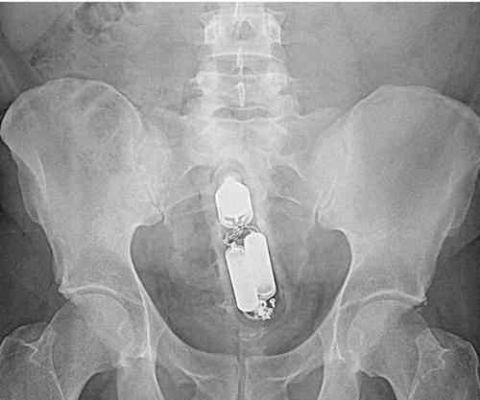

这里面装的*品毒**